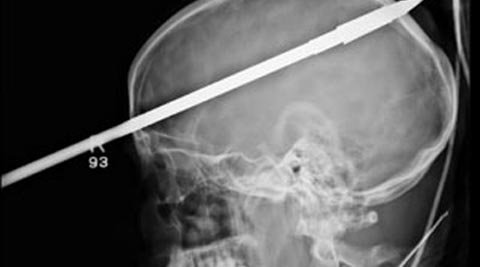

Tên xuyên qua não, vẫn sống sót

Các bác sĩ ở Miami, Mỹ đã gỡ bỏ thành công mũi tên vô tình đâm trúng hộp sọ của một thanh niên trong lúc đi dã ngoại.